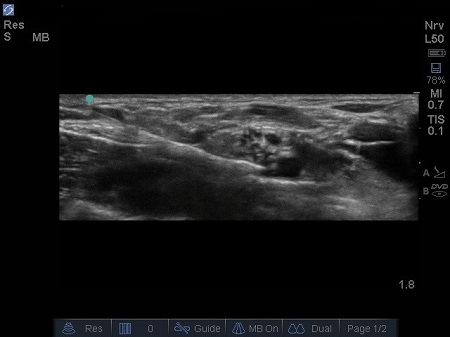

- Lateral and above the artery sit a bundle of round hypoechoic circles (“bunch of grapes” or “cluster of bubbles”) – the brachial plexus, at this level, the plexus will be configured as trunks and/or divisions.

- It may be possible to identify the hypoechoic nodules surrounded by a hyper-reflective fascial sheath.

- Local anaesthetic (LA) should spread around the hypoechoic circles causing hydro dissection of the planes. (5) See 6. & 7.

Fig. 6. Initial injection of LA, note proximity to subclavian artery. Excellent needle control is required to safely perform this technique.

Fig. 7. Increasing spread of LAj